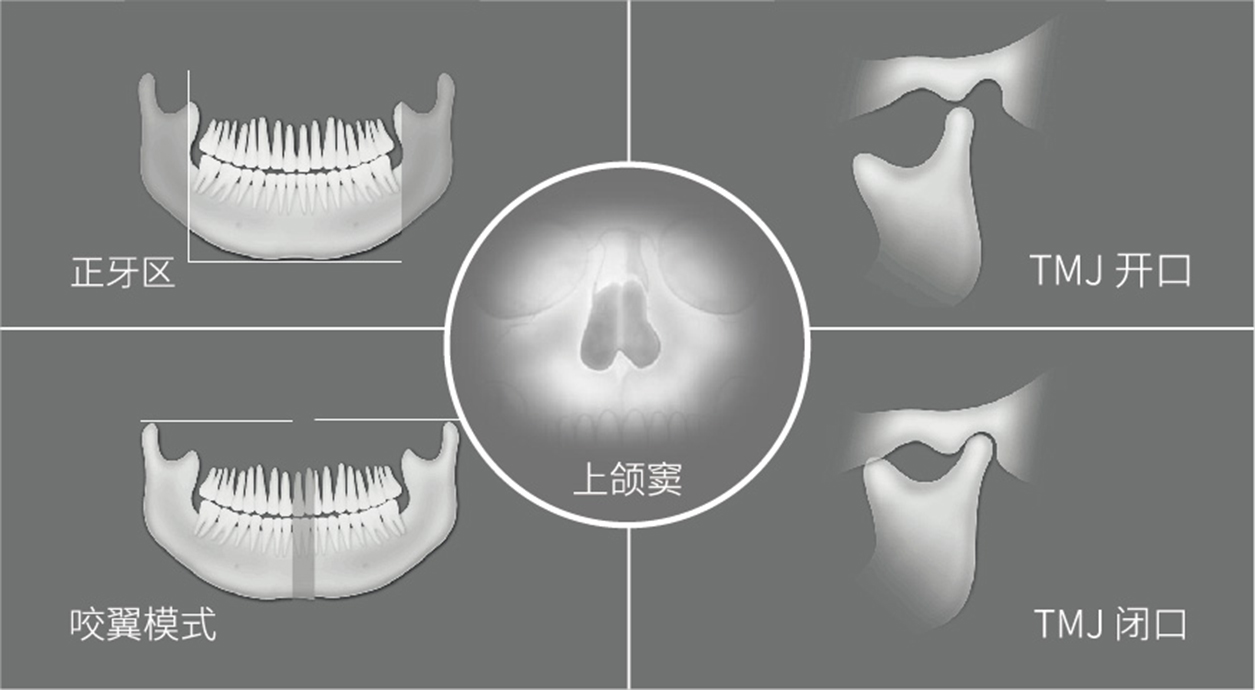

一次扫描获取21张影像,将每张清晰的区域自动重建为一张高清影像,大大节省了重新拍摄以及和患者沟通的时间。同时可清楚拍摄前牙区、根尖区、上颌窦底、TMJ等部位的口腔影像。

全景影像含多种拍摄的功能:有单独的上颌窦区域、TMJ开口、TMJ闭口等。可以根据用户需求进行拍摄。